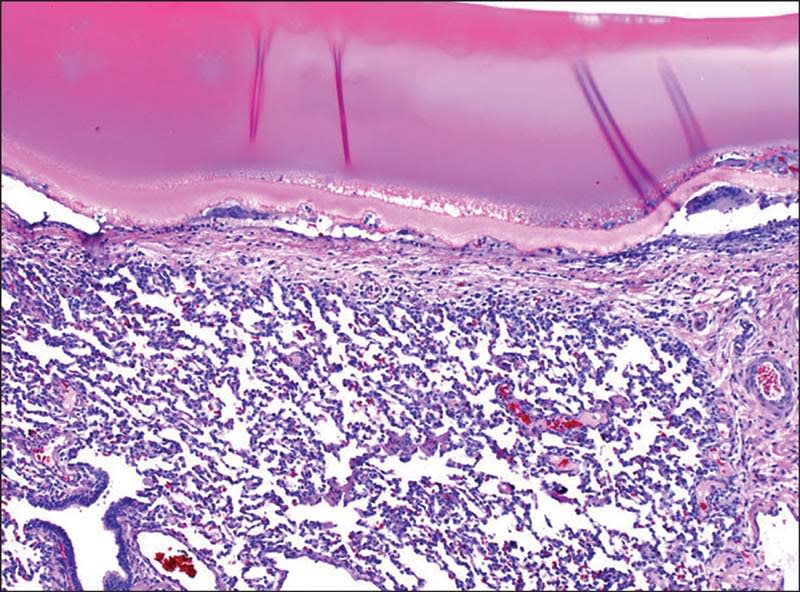

The researchers demonstrated that a sealant, based on elastin — a human, resilience-imparting protein present in all elastic tissues such as the wall of arteries, skin, and lungs — can be photo-chemically tuned to effectively seal incisions in arteries and lungs of rats and to repair wounds in the lungs of pigs, all suture and staple-free. Khademhosseini is also a professor at Harvard-MIT's Division of Health Sciences and Technology and Brigham and Women's Hospital and Annabi is assistant professor at the department of chemical engineering at Northeastern University and lecturer at the Harvard-MIT's Division of Health Science and Technology.

These new MeTro gels could seamlessly close incisions in arteries and punctures in lungs of live rats, allowing the animals that otherwise would have succumbed to the procedure to survive. “The beauty of a MeTro formulation is that, as soon as it comes in contact with tissue surfaces, it solidifies into a gel-like phase without running away. We then can further stabilize it by curing it on-site with a short light-mediated crosslinking treatment. This allows the sealant to be very accurately placed and to tightly bond and interlock with structures on the tissue surface,” says Annabi.

To translate their findings further toward more human-like lung injuries, the team first tested whether MeTro could also seal incisions in explanted and deflated lungs of pigs. Upon inflation, MeTro was significantly more effective at sealing the leaks under higher pressures than clinically available sealants and sutures. Importantly, this trend held up in in vivo experiments in which MeTro could permanently seal severe pulmonary air and blood leakages, again without applied staples or sutures.